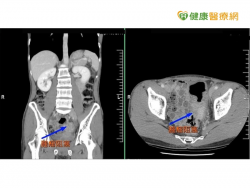

大腸癌年輕化 腹脹血便是徵兆 33歲男突然腹脹腹痛 竟是大腸癌第三期 一名33歲莊先生,長期有抽菸習慣,飲食上也以外食居多,前幾天開始出現腹脹腹痛等重撞,雖無明顯血便,但急診檢查後,就發現不僅腸道完全阻塞,甚至出現嚴重腹脹和嘔吐現象;就醫後經電腦斷層掃描後發現,有一個約6公分的乙狀結腸腫瘤阻塞腸道,採腹腔鏡手術切除後,確診為大腸癌第三期,目前接受...... [閱讀更多]